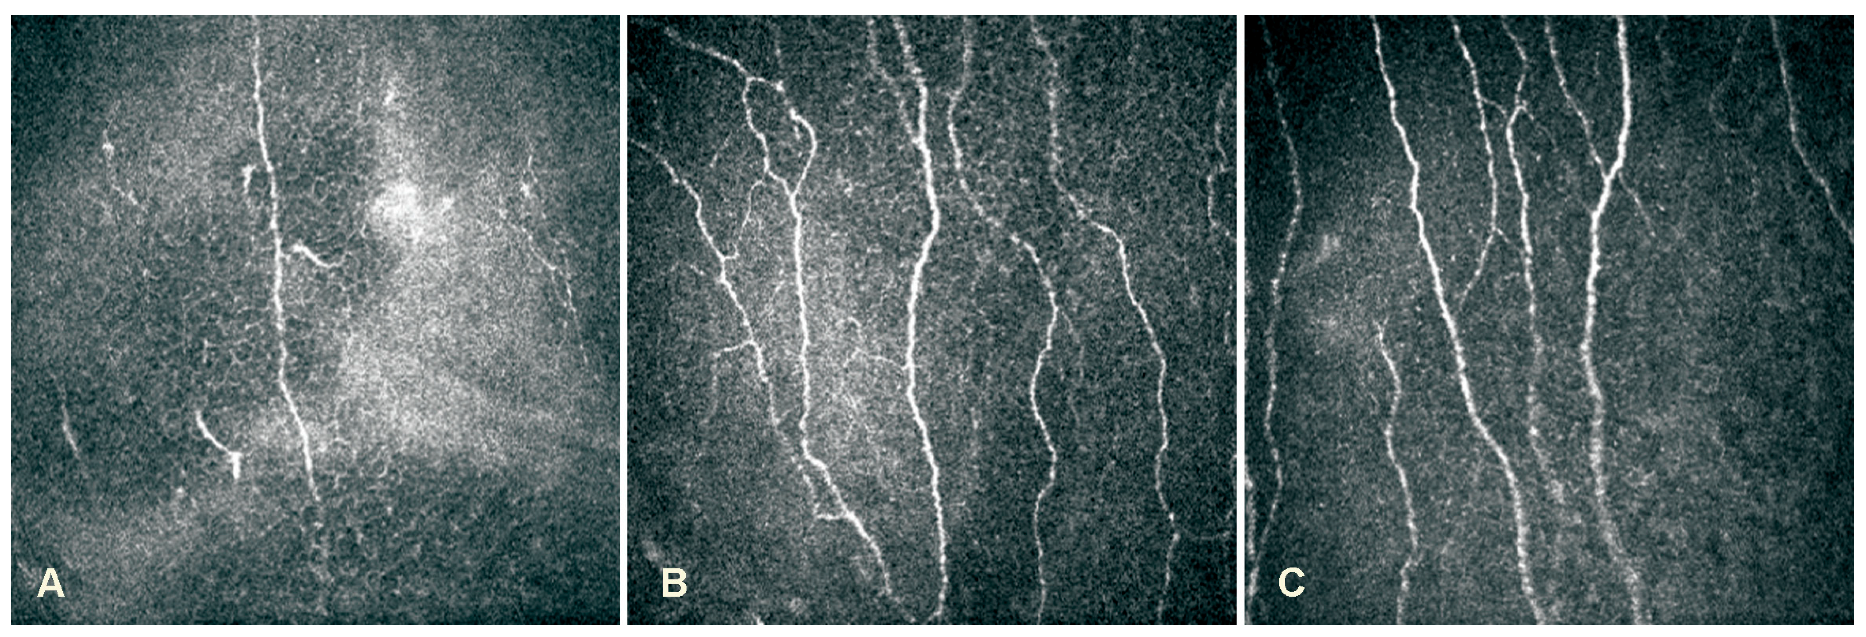

HSVaffected eyes showed a reduction in the mean corneal sensitivity and sub-basal nerve parameters and an increase in the mean intraocular pressure when compared with contralateral eyes, herpes labialis and healthy control group eyes (p < 0.05). The mean corneal sensitivity and sub-basal nerve parameters of contralateral eyes were also different comparing with herpes labialis patients and healthy controls (p < 0.05). There was no difference between herpes labialis and healthy control group eyes (p > 0.05). Data of all groups and subgroups are presented in Table 2. LSCM images of corneal sub-basal nerve plexus are demonstrated in Figure 1.

Figure 1.

LSCM images of corneal sub-basal nerve plexus: (A)–HSV keratitis with severe sensation loss; (B)–Herpes labialis patient; (C)–Healthy person.